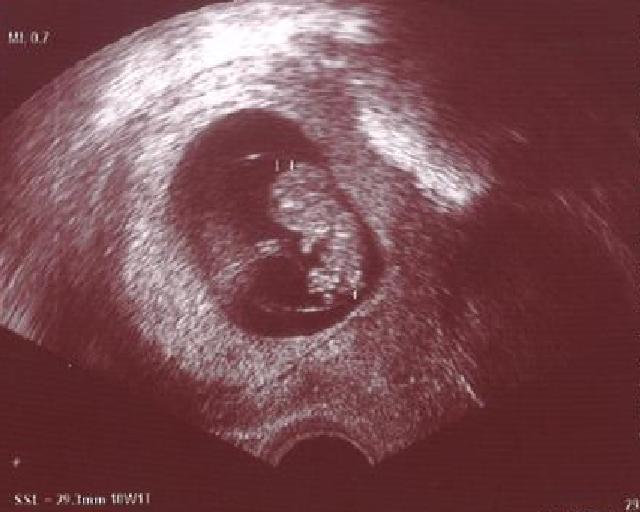

Wow, katz-LE, richtig schönes Bild, normalerweise erkennt man doch kaum was, aber hier ist der Wunderkrümel ja richtig fotogen!